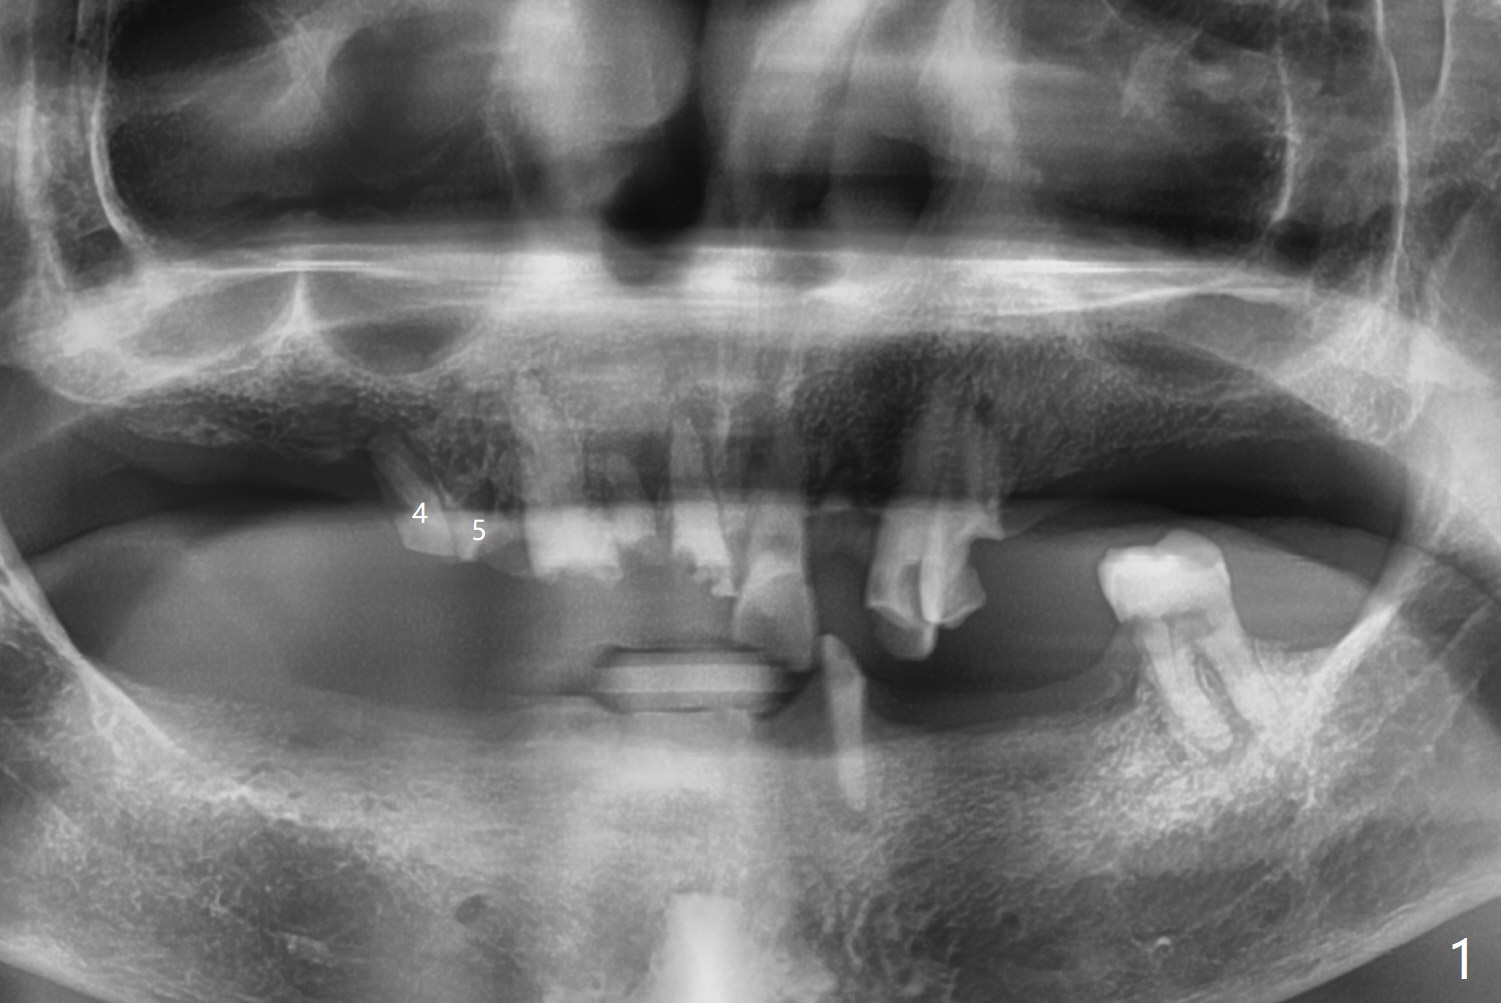

A 84-year-old man has upper right discomfort. Exam shows #4,5 residual roots have percussion pain, while the apex of #4 is buccally exposed (Fig.1). After extraction of #4 and 5 and debridement, collagen plug is inserted to the buccal defect. Then cortical allograft is placed in the sockets and covered with 8x8 mm BioXclude. The wound is approximated with 4-0 PGA suture. With use of BioXclude, the bone graft appears to remain in place 8 days postop (Fig.2,3). The apical perforation at #4 seems to be healing (Fig.2 >).